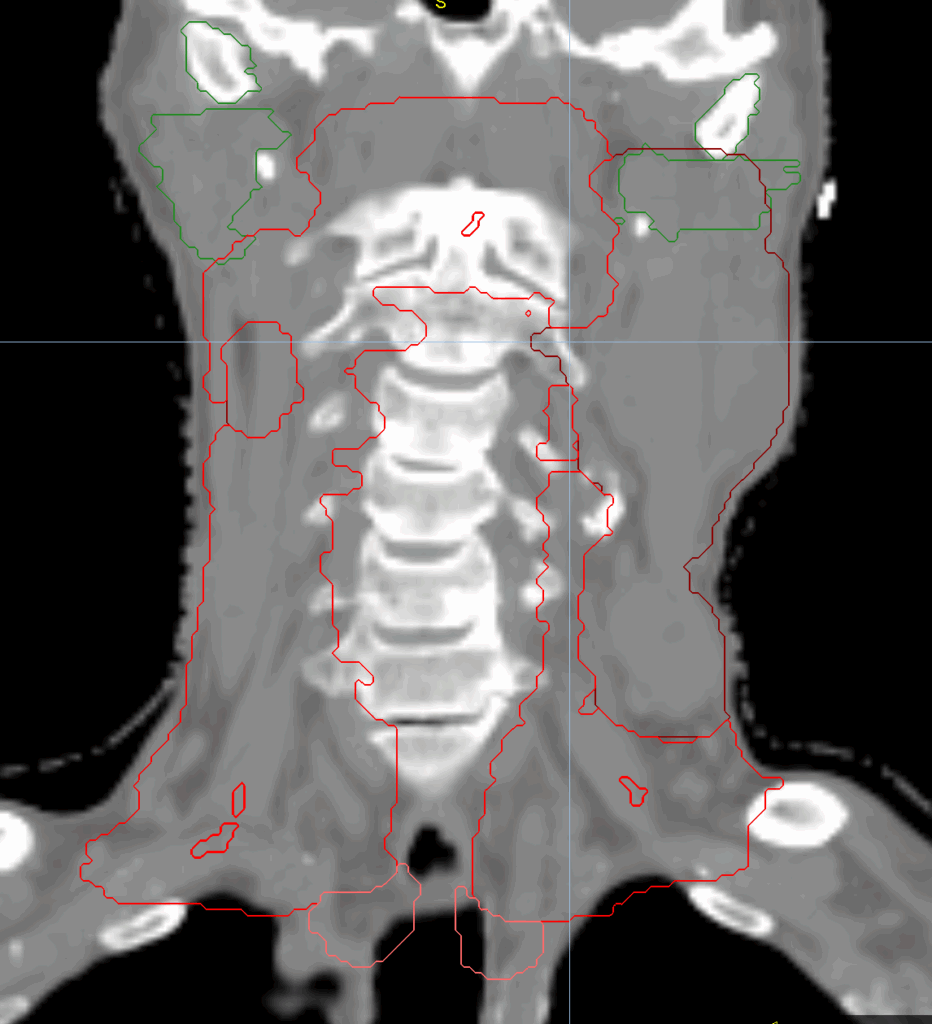

Planning CT Images

Treatment Plan Images